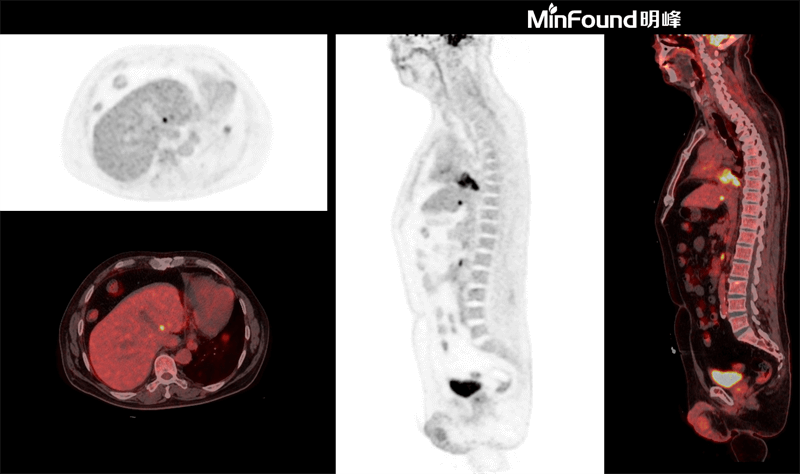

ScintCare PET/CT 730T

ScintCare PET/CT 730T employs a 4th-generation PET detector where lutetium-yttrium oxyorthosilicate (LYSO) crystals are individually coupled to SiPM detectors without the optical conductor (1: 1 coupling and 100% coverage). The digital SiPM detector considerably minimizes photon loss, resulting in improved time resolution (380 ps), system sensitivity (23.5 cps / kBq), and image uniformity, ultimately resulting in high-resolution images under well-curated radiation dose control.

ScintCare PET/CT 730T axial FOV reaches 40.3 cm width, enabling the whole-organ scan just by one-bed position and the whole-body scan by two-bed positions in about 3 minutes time. The ultra-fast data acquisition greatly supports the large patient throughput.

臨床畫廊